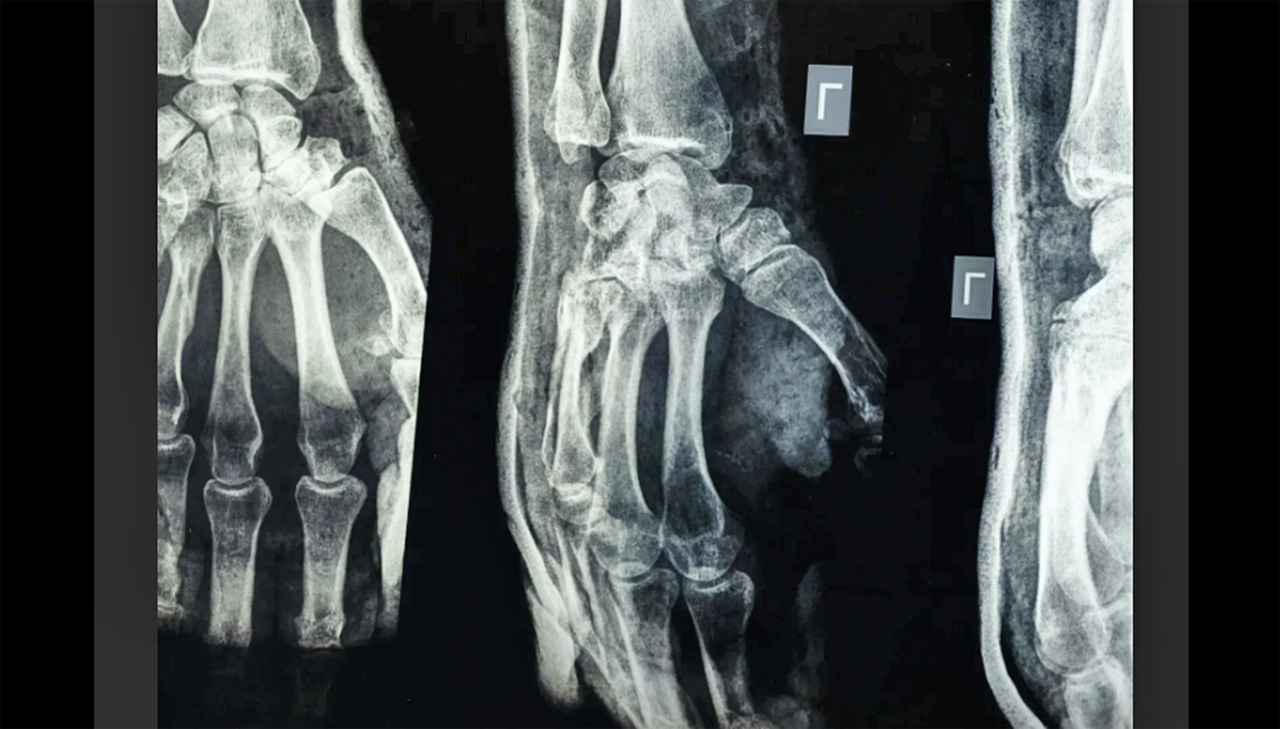

Testele de laborator și studiile clinice pe peste 150 de pacienți au arătat că „Bone-02” oferă o rezistență comparabilă cu cea a implanturilor metalice, având o forță de lipire de peste 400 de livre și o rezistență la compresiune de circa 10 MPa.